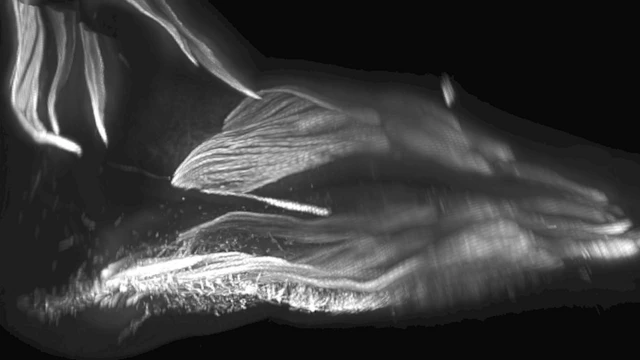

Janin-janin di rahim memiliki otot tambahan mirip kadal di tangan mereka yang sebagian besar akan hilang sebelum bayi-bayi ini dilahirkan, itulah yang terungkap dalam pemindaian medis.

Kondisi ini kemungkinan adalah salah satu sisa evolusi yang tertua, meskipun hanya muncul pada masa yang singkat pada rahim, tulis para ahli biologi di jurnal Development.

Otot yang telah berumur 250 juta tahun ini merupakan peninggalan yang masih ada saat reptil bertransisi menjadi mamalia.

Kadang-kadang ditemukan anak-anak atau orang dewasa yang memiliki jari tambahan dan otot tangan, tetapi tidak pernah keseluruhan otot-otot tangan dapat dilihat ahli biologi saat mereka mengamati pemindaian 3D embrio dan janin pada usia kehamilan tujuh sampai 13 minggu.

Mereka telah meneliti kaki dan mengetahui adalah otot tambahan yang tumbuh dan juga menghilang ketika bayi tumbuh di dalam rahim.

Monyet dan kera masih memiliki otot ini dan menggunakannya untuk memanjat atau memegang benda dengan kaki mereka.